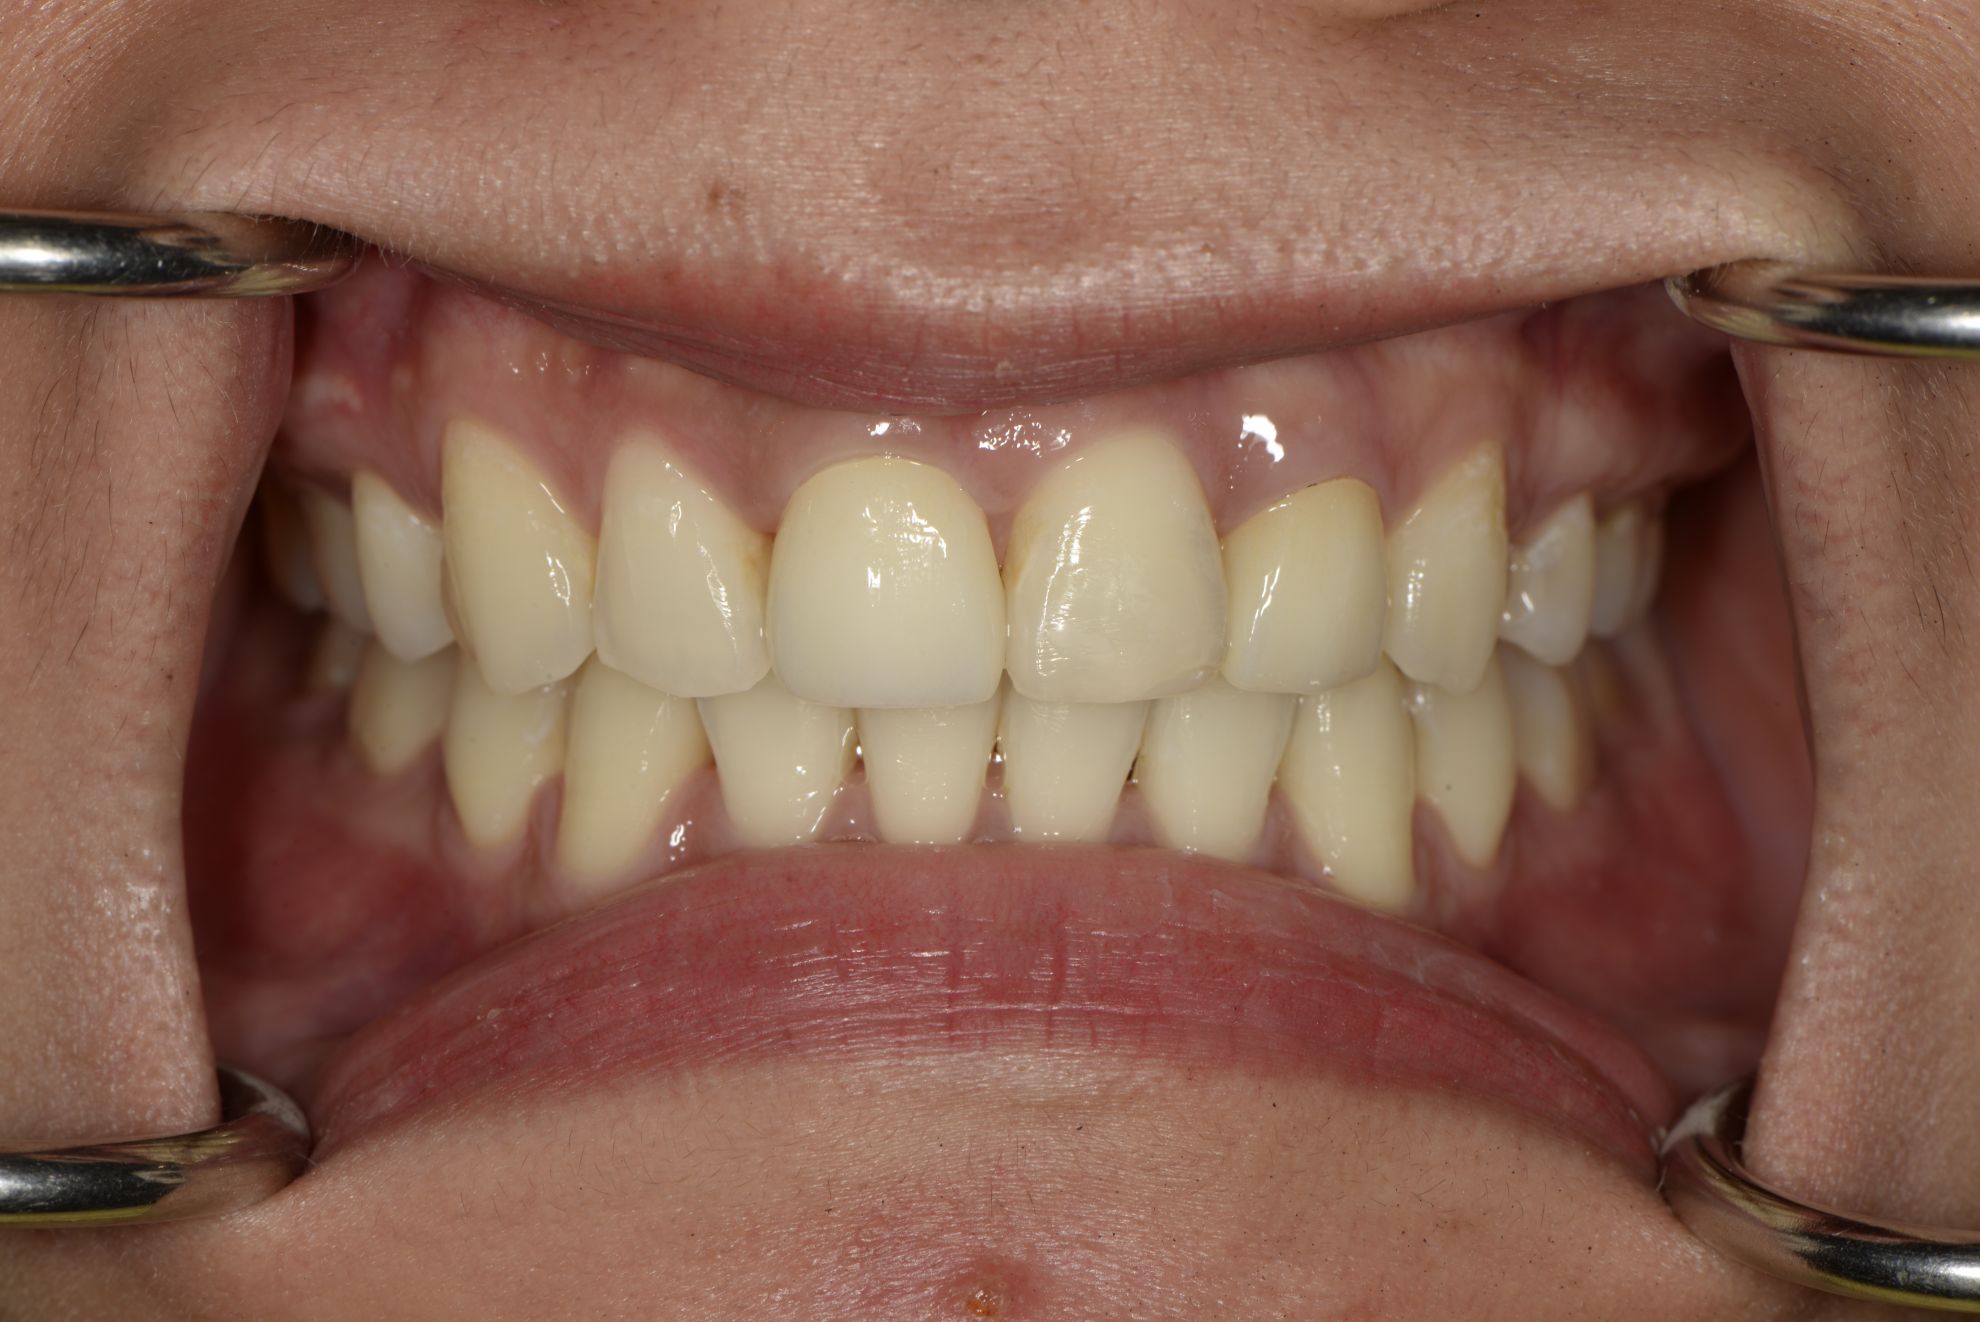

Before

• 牙齒染色

• 茶垢、菸垢附著

After

• 全口噴砂